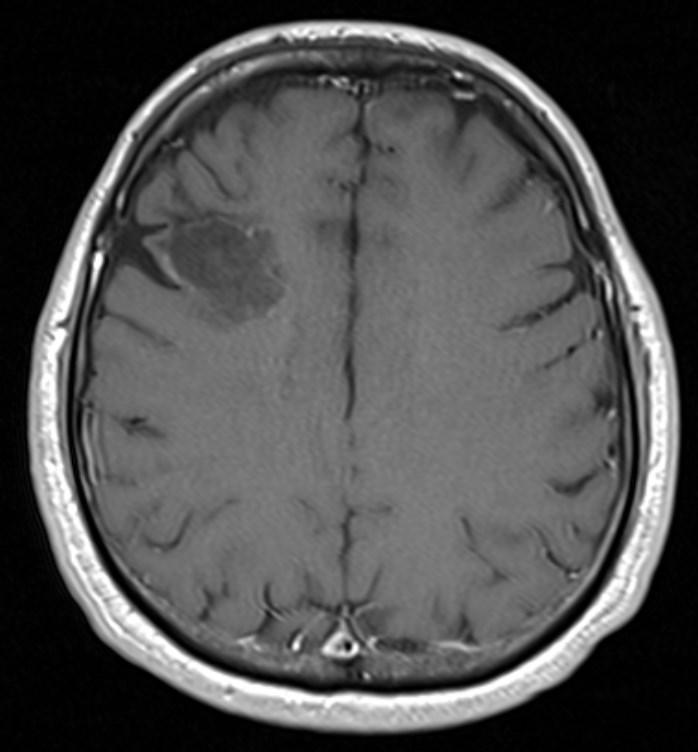

Answer: Primary hydatid cyst of right frontal lobe.

MR images revealed Gharbi type V hydatid cysts in right frontal lobe.

Gharbi classified hydatid cyst ultrasonographic images into 5 types: Type 1, walled, unilocular, anechoic; type 2, separated membranes; type 3, multisepta, daughter vesicles; type 4, heterogenic, hypo-hyperechogenic; type 5, calcification of a section of the wall or completely calcified (4). The cysts characteristically have three components: Pericyst, Exocyst, and Endocyst.